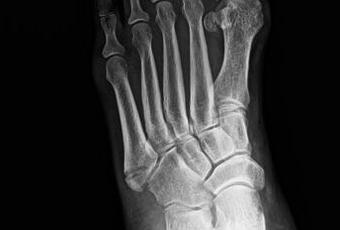

Se visualiza trazo de fractura en base de 5to metatarsiano, de disposición transversal, sin diástasis de

FRACTURA DE BASE DE 5TO METATARSIANO.